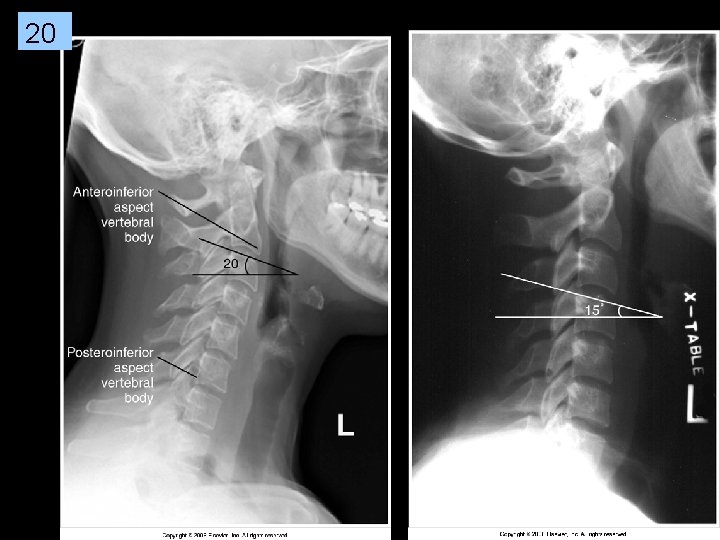

19 Some rotation ((zygo & pillars not s/i) & TILT